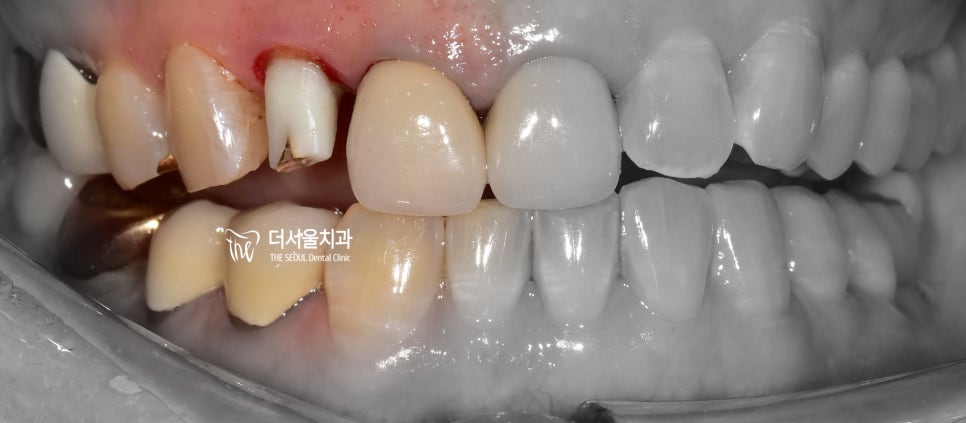

『선생님, 저 치아가 부러졌습니다.』

이미 과거에 신경치료를 받으셨던 이력이 있고,

구강 위생 관리에 소홀하셨다가 또 다시

우식증 발생에 따라서 치관이 파절이 되어

저를 찾아오셨던 분이 계셨었습니다.

정면에서 보면 공간이 비어있죠?

비심미적인 모습을 갖고 있을뿐더러,

이미 어느정도의 통증을 호소하셨던 분입니다.

이렇게 되면 치아를 발치를 해야 되는가?

선택을 해야 됩니다.

물론, 예전에 신경치료 를 받으셨기 때문에

이 분의 경우 재신경치료 과정을 거쳐야 되며

치관 자체가 파절이 되었기 때문에,

포스트 코어(클릭) 라 해서 인공기둥을 만들어

크라운과 연결이 될 수 있는 방식을

선택해야 됩니다.